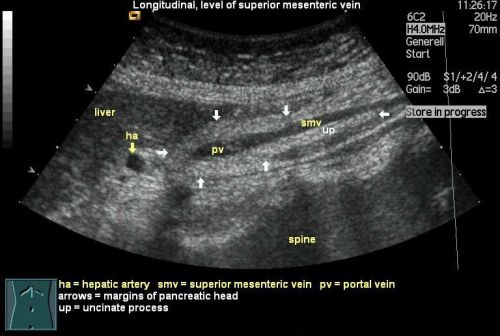

УЗИ поджелудочной железы

При проведении УЗИ оцениваются все параметры поджелудочной

Кроме этого, врач изучает состояние сосудов, располагающихся внутри органа и возле него, что позволяет дать оценку кровоснабжения железы. В случае, если при исследовании поджелудочной железы на УЗИ были выявлены какие-либо отклонения от нормы, врачом проводятся различия между аномалиями железы. Перед ним стоит нелегкая задача отличить воспаление от опухоли, возрастные изменения в органе от хронического панкреатита и т.д.